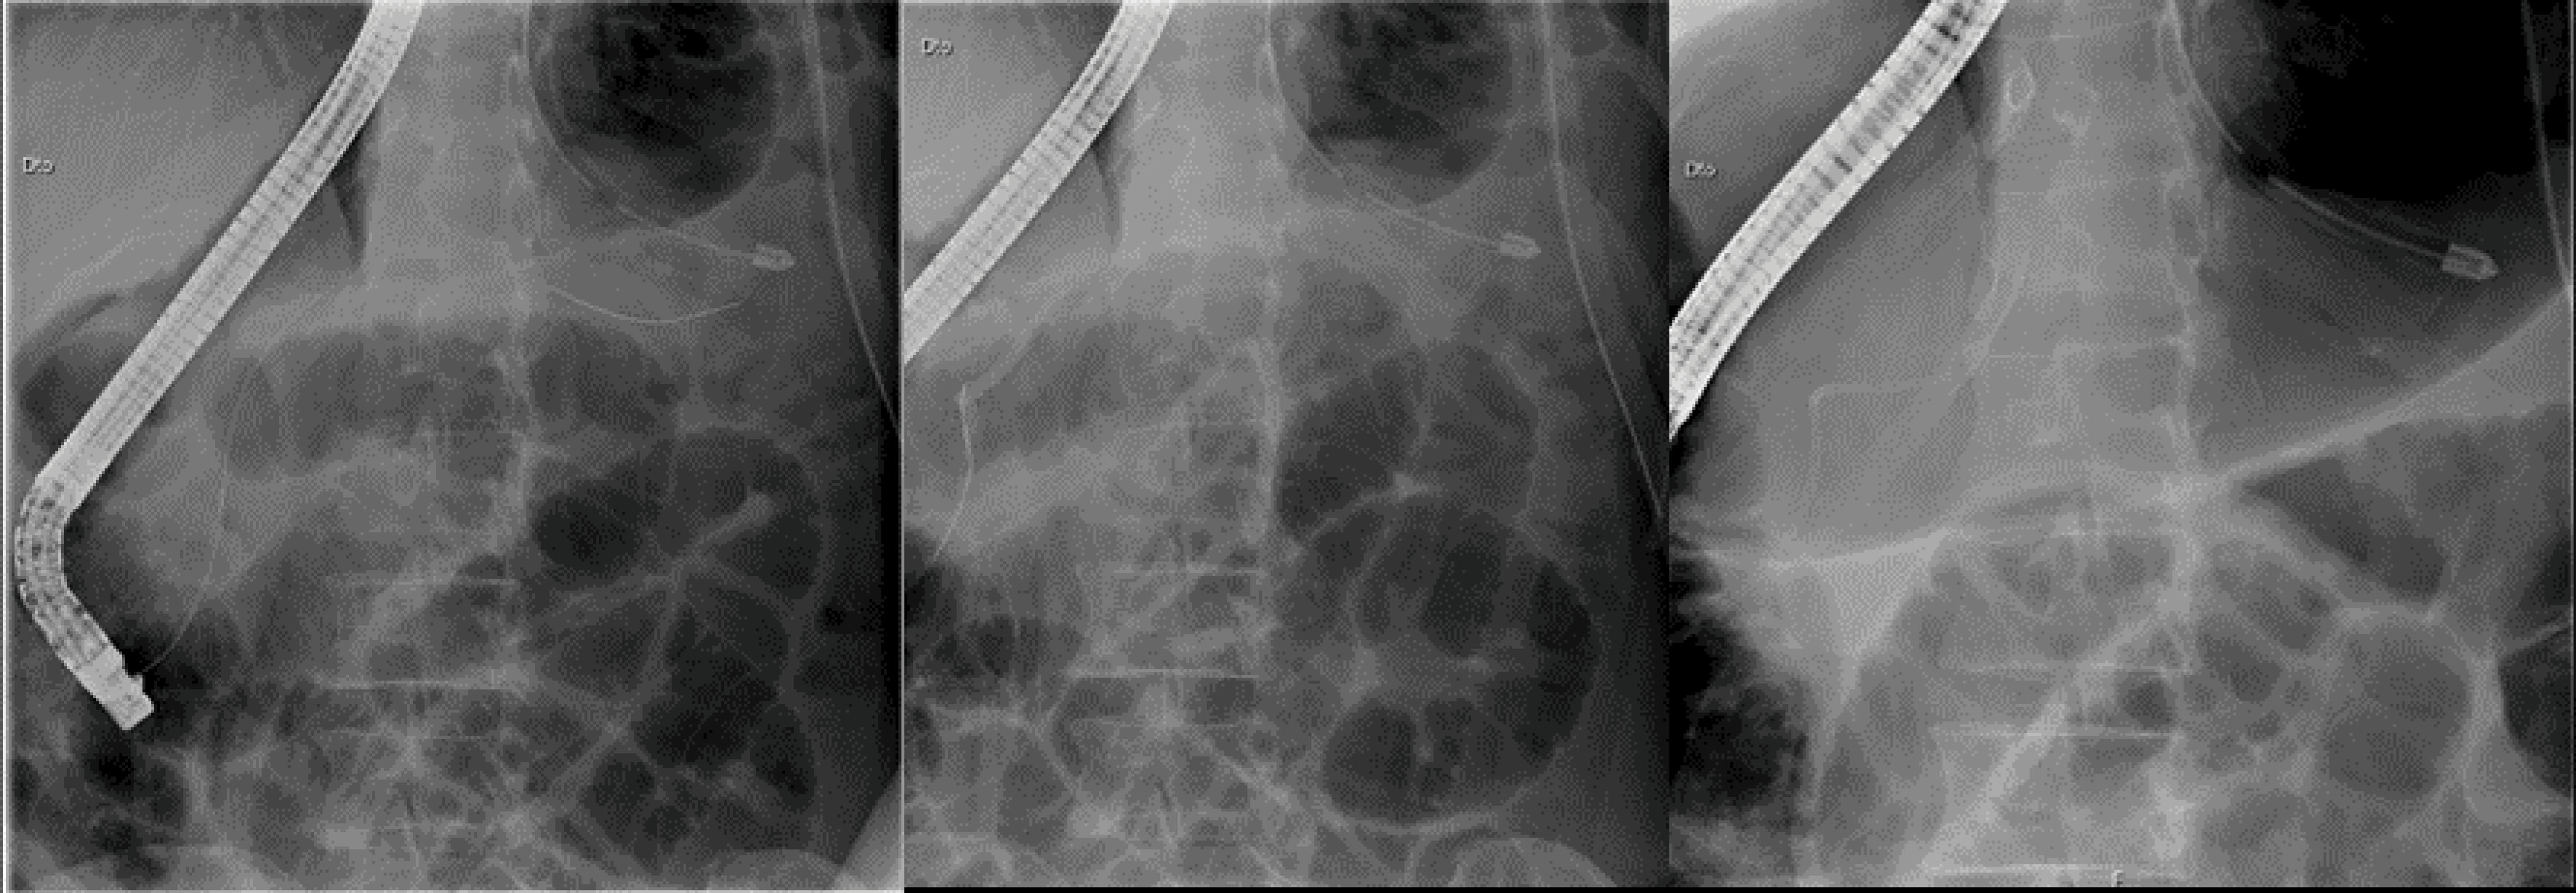

At that consultation, an elective hospitalization (3 weeks after the first thoracentesis) for pleural drainage, medical care (parenteral feeding and administration of octreotide) and endoscopic (ERCP) treatment was decided. During ERCP, a sphincterotomy was performed and a leak of contrast (high output) was shown in the Wirsung duct; a prosthesis was placed in the proximal region of the evidenced fistulous path (). At discharge date (3 days after stent placement), there was no longer significant pleural effusion. The monthly intramuscular octreotide was continued. After three months, the MRCP was repeated, with no sign of pleural effusion and a total resorption of the pseudocyst. With these results a total resolution of the fistulous path was assumed and a new ERCP was scheduled to remove the pancreatic prosthesis.

jcvtr-14-67-g003

Figure 3. Endoscopic Retrograde Cholangiopancreatography (ERCP) procedure